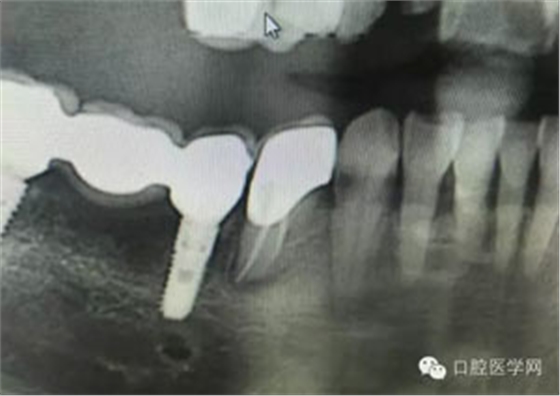

病例1:患者迫切希望保留自己的這一顆牙齒,根尖周陰影比較大,二度松動(dòng).而且旁邊有種植修復(fù)體,和患者溝通好后,治療好后觀察一個(gè)月后冠修復(fù),因?yàn)橛蟹N植的后期修復(fù),所以有了機(jī)會(huì)觀察,術(shù)后三個(gè)月和術(shù)后四個(gè)月,根尖恢復(fù)的還算不錯(cuò),希望能夠繼續(xù)觀察下去.這樣子的病例,做的時(shí)候我們一定要非常的小心,和患者要有充分的溝通以及不同科室的溝通然后決定怎么樣做比較好,假如就是出現(xiàn)了問題,到時(shí)候我們也比較好處理些,免得我們自己到時(shí)候不好收?qǐng)觥?/span> 病例2:364647中齲的樹脂充填,現(xiàn)在樹脂的充填材料非常之多,有些時(shí)候,我們感覺有了好的材料我們就可以做出好的修復(fù),可是這是在我們有扎實(shí)的基本功的基礎(chǔ)上的,我們可以沒有那么好的樹脂,那么多的顏色選擇,修復(fù)的那么的逼真,但是我們至少要恢復(fù)患者牙齒的功能,將腐質(zhì)去除干凈,薄壁弱尖消除掉,選擇好適應(yīng)癥,給患者以盡可能好的修復(fù)。 來源于KQ88